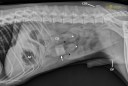

Une souris bionique, voilà ce qu’il avait mangé !